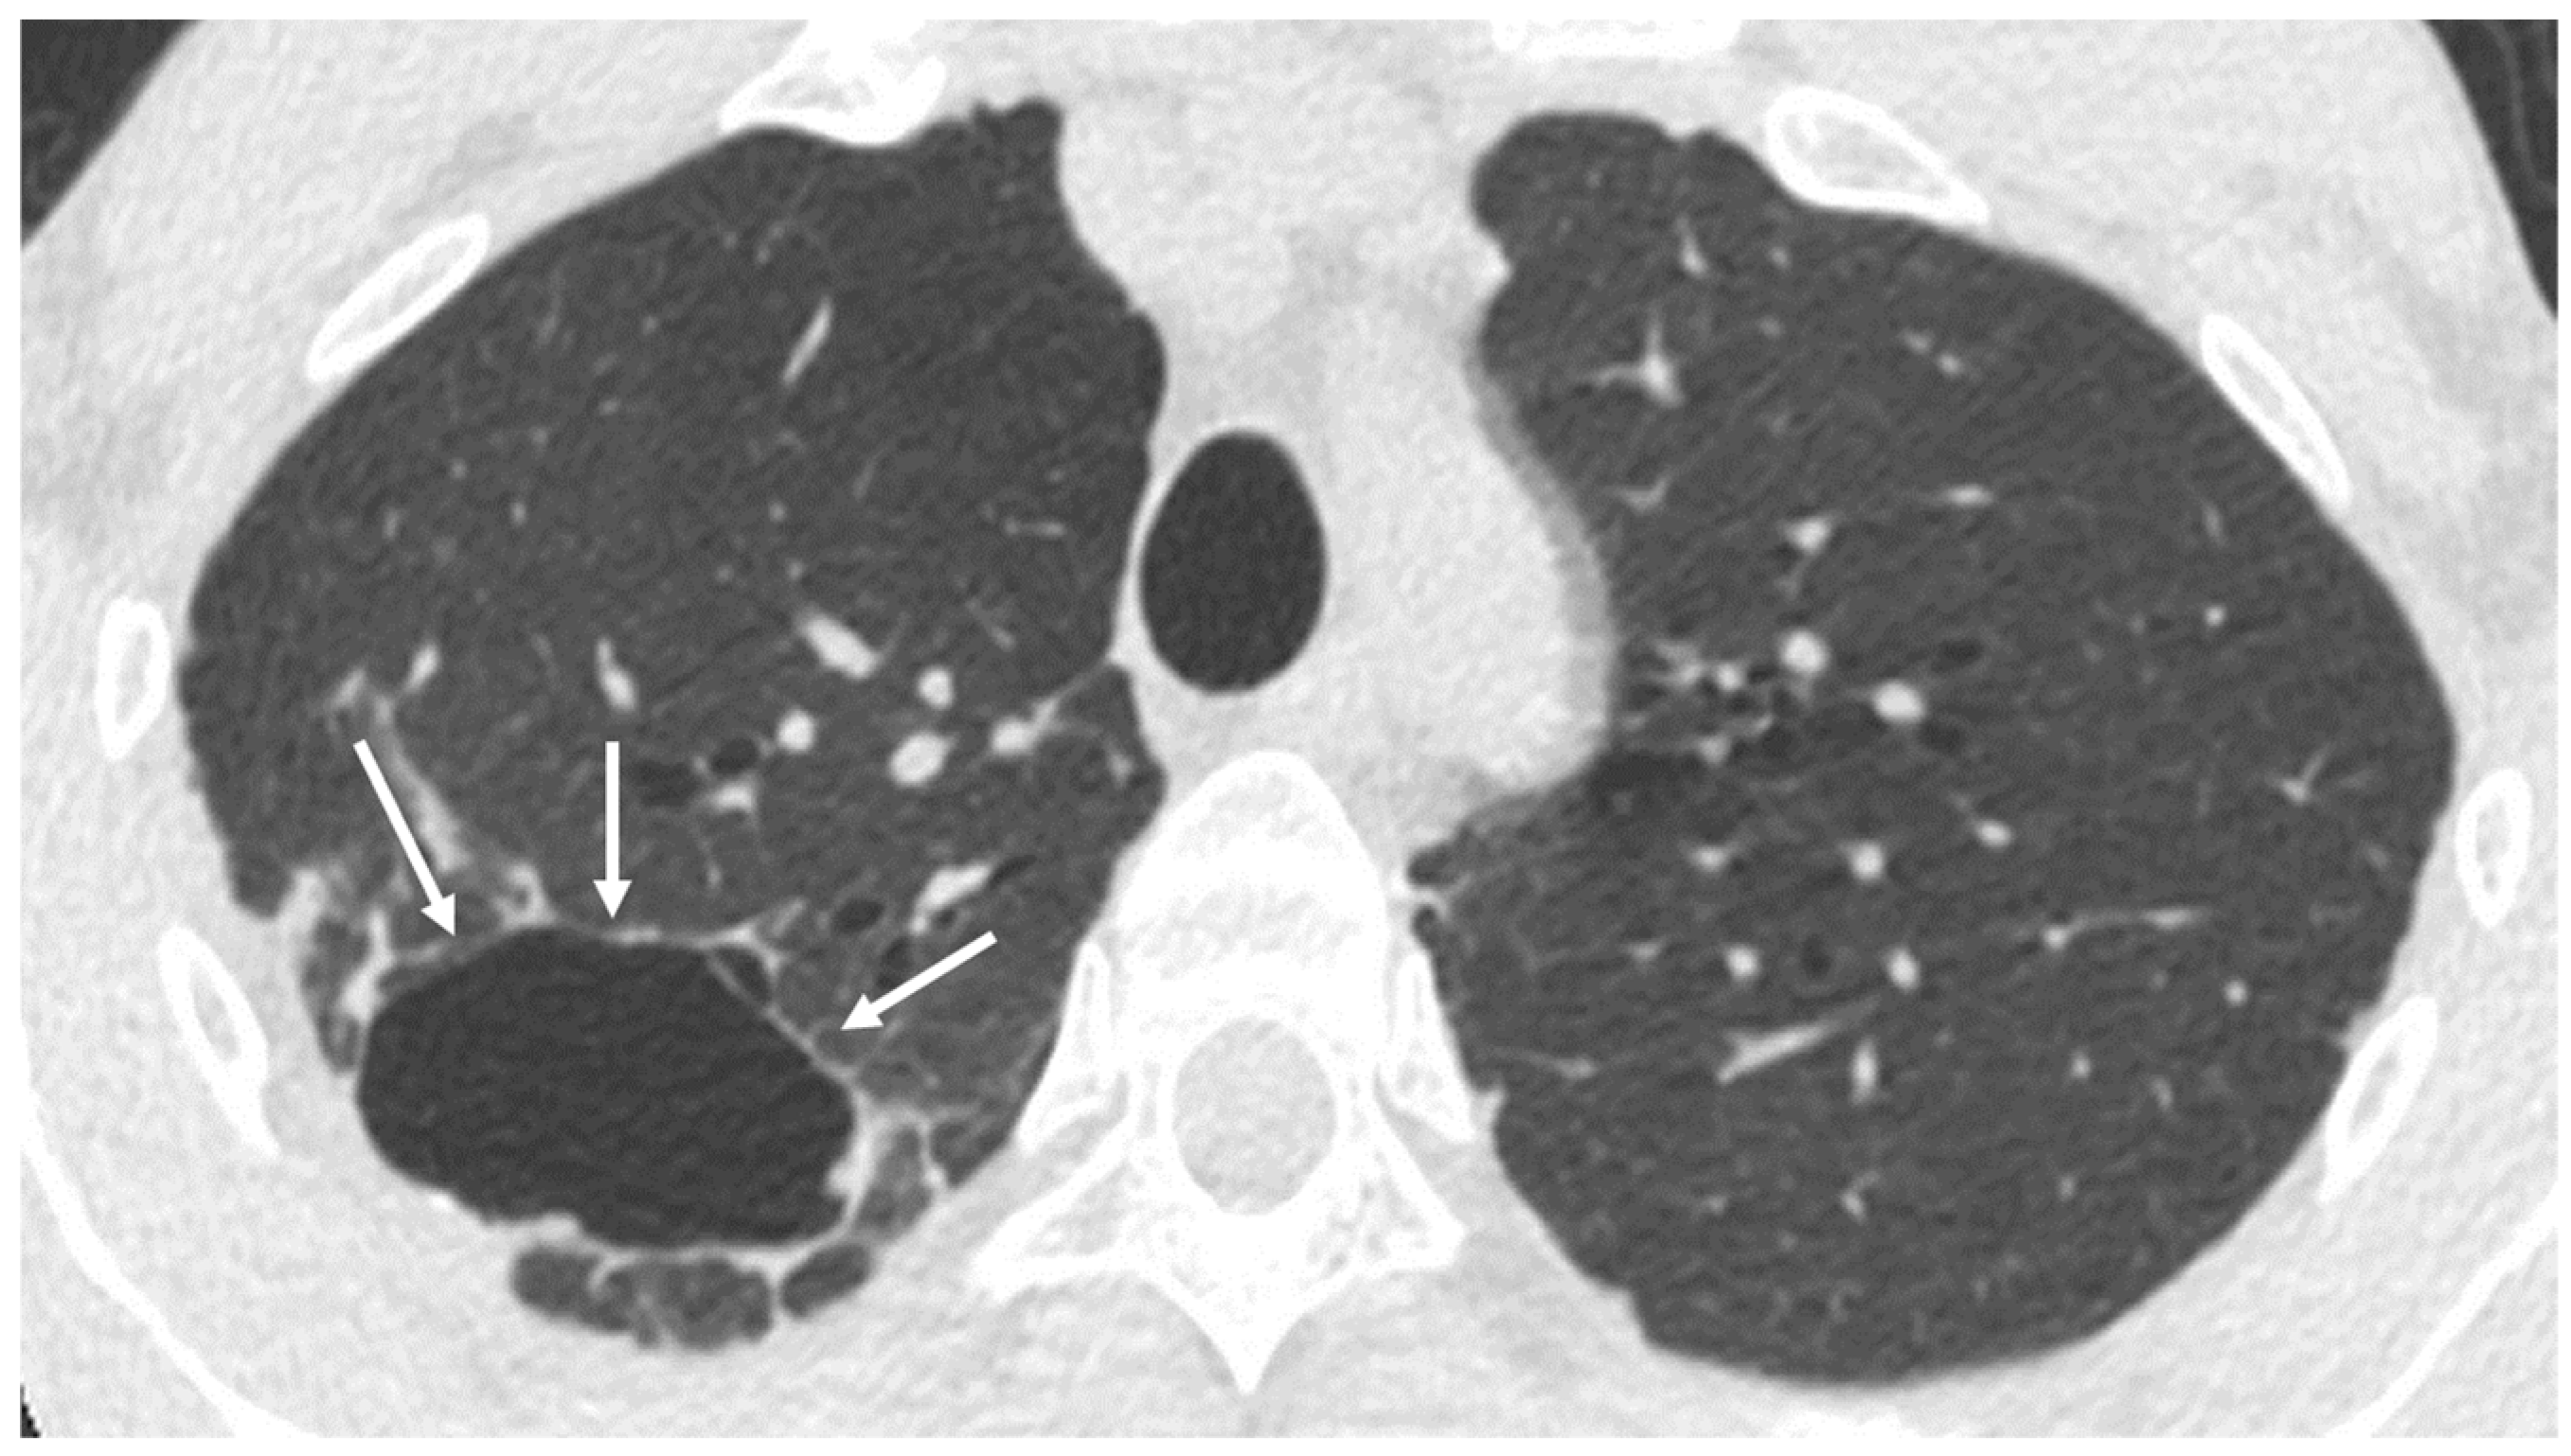

3.3. Bronchiectasis